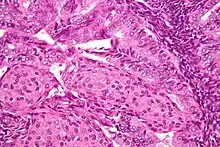

.jpg.webp)

In endometrioid adenocarcinoma, the cancer cells grow in patterns reminiscent of normal endometrium, with many new glands formed from columnar epithelium with some abnormal nuclei. Low-grade endometrioid adenocarcinomas have well differentiated cells, have not invaded the myometrium, and are seen alongside endometrial hyperplasia. The tumor's glands form very close together, without the stromal tissue that normally separates them. Higher-grade endometrioid adenocarcinomas have less well-differentiated cells, have more solid sheets of tumor cells no longer organized into glands, and are associated with an atrophied endometrium. There are several subtypes of endometrioid adenocarcinoma with similar prognoses, including villoglandular, secretory, and ciliated cell variants. There is also a subtype characterized by squamous differentiation. Some endometrioid adenocarcinomas have foci of mucinous carcinoma.[44]

The genetic mutations most commonly associated with endometrioid adenocarcinoma are in the genes PTEN, a tumor suppressor; PIK3CA, a kinase; KRAS, a GTPase that functions in signal transduction; and CTNNB1, involved in adhesion and cell signaling. The CTNNB1 (beta-catenin) gene is most commonly mutated in the squamous subtype of endometrioid adenocarcinoma.[45]